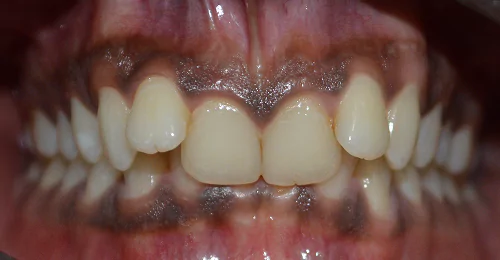

Orthodontic Case – III

(Case Done by Dr. Sonali Deshmukh M.D.S. / Orthodontist )

Deep – II Correction

Pre Treatment